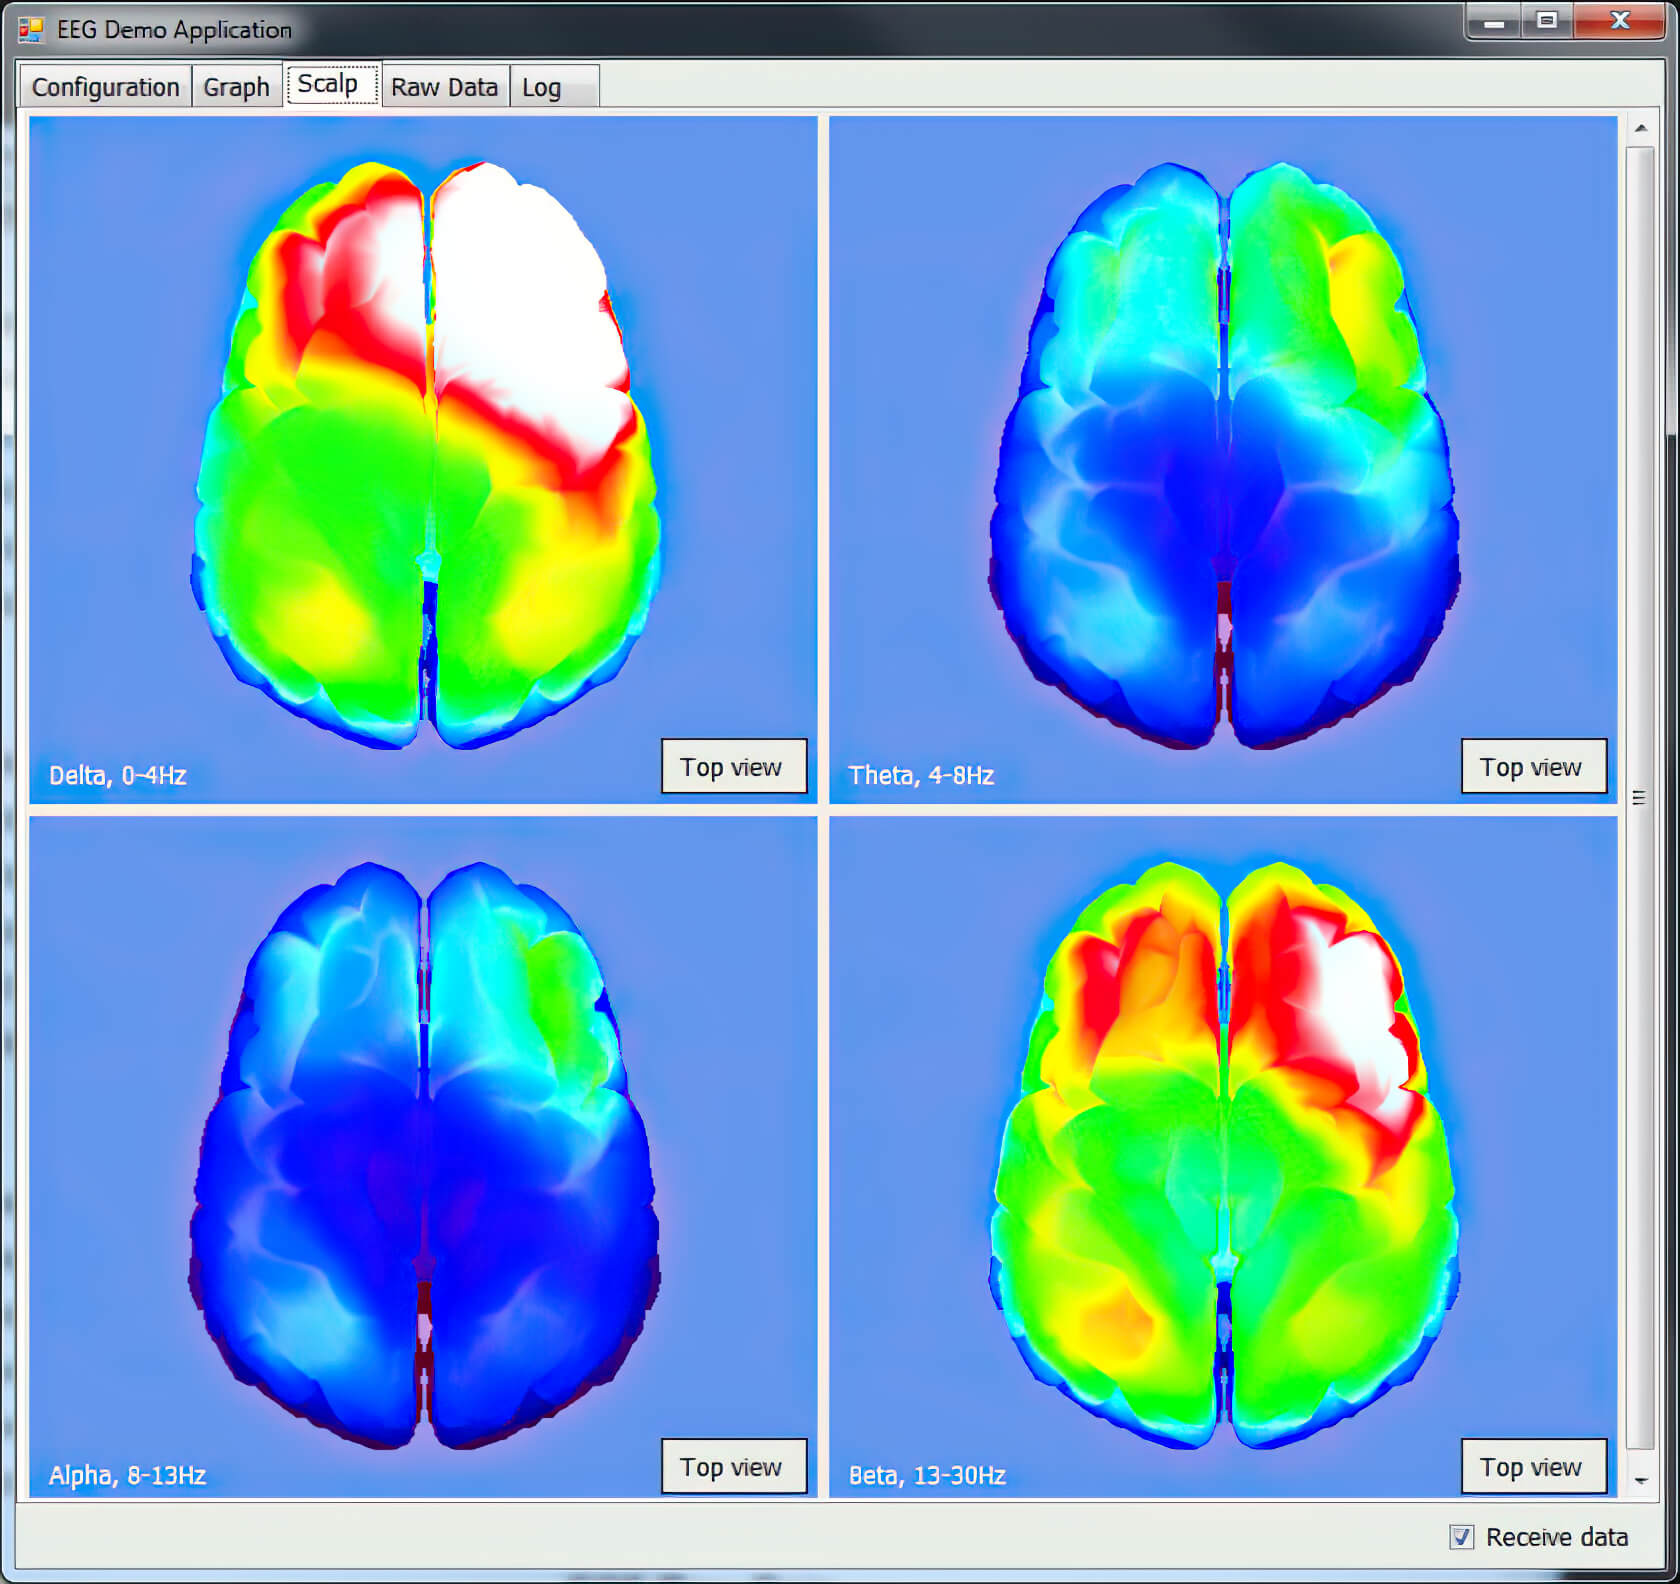

Визуализация

Проводит частотный анализ, анализирует гармоники (альфа, бета, тета, дельта-ритмы) и визуально отображает их на 3D модели головного мозга. Данные могут приходить как прямо с устройства в реальном времени, так и быть загружены из проведенных ранее сеансов.